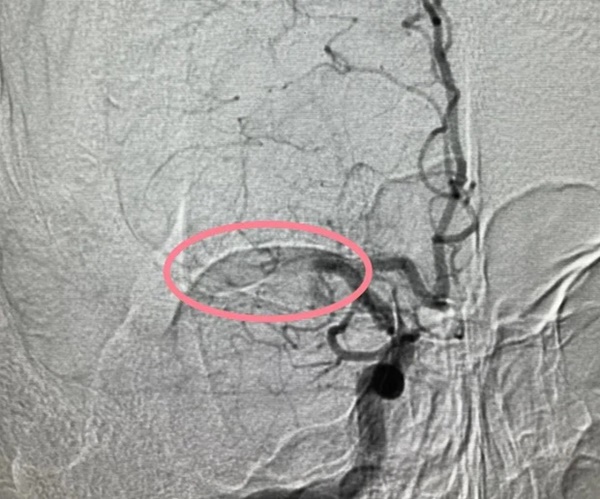

Một cục huyết khối làm tắc động mạch não giữa

Vào chiều ngày 2/2 vừa qua, Tiểu Vương đột nhiên cảm thấy yếu sức chân trái khi đang ở nhà, anh cũng không thể nhấc tay trái lên được và nói ngọng nghịu. Gia đình vội đưa anh đến bệnh viện địa phương, chụp CTA đầu cho thấy đoạn M1 của động mạch não giữa bên phải đã bị tắc. Tiểu Vương bị nhồi máu não khi còn trẻ như vậy!

Bác sĩ Lưu Phương Kỳ, Phó trưởng Khoa Phẫu thuật mạch máu can thiệp của Bệnh viện Nhân dân tỉnh Hồ Nam, đã thực hiện chụp mạch máu não và phẫu thuật lấy huyết khối cho Tiểu Vương

Bác sĩ Lưu Phương Kỳ đã dẫn đầu kíp trực, tiến hành chụp mạch não và phẫu thuật lấy huyết khối nội mạch cho Tiểu Vương. Sau ca phẫu thuật, Tiểu Vương đã lấy lại được khả năng nói lưu loát và chi trái có thể tự do nâng lên.